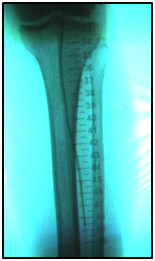

Endovascular procedure was done with antegrade access in the ipsilateral common femoral artery, diagnostic angiography confirmed: Patency of the femoral-popliteal axis, occlusion of the posterior and anterior tibial arteries, two critical stenotic lesions in the fibular artery and revascularization of the dorsalis pedis and plantar arteries by the fibular artery. To treat the fibular critical atherosclerotic lesions were performed a percutaneous transluminal angioplasty using a 0.0018in.guidewire, catheter support and a catheter balloon (3,0x6 mm and 3,5x 15mm).

Final angiographic control showed patency of the fibular artery and dorsalis pedis, with direct flow for the first metatarsal artery, thus guaranteeing enough flow to heal the ulcer in six months after the procedure. In conclusion endovascular treatment has a high technical eligibility with good reported outcomes and represents an alternative for diabetics with CLI Disease (Figure 1 and 2).

• Figure 1 Angiography from left to right showing femoral-popliteal axis, occlusion of the posterior and anterior tibial arteries, in detail two critical stenotic lesions in the fibular artery.

• Figure 2 From left to right showing percutaneous transluminal BTK balloon angioplasty, and revascularization of the dorsalis pedis and plantar arteries by the fibular artery.